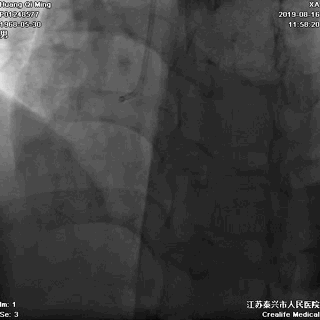

冠状动脉造影

右冠状动脉无严重狭窄

左主干前分叉处血管正常

LCX近中段病变,狭窄最重达90%

LAD中远段血管偏细,弥漫性病变,狭窄达90%